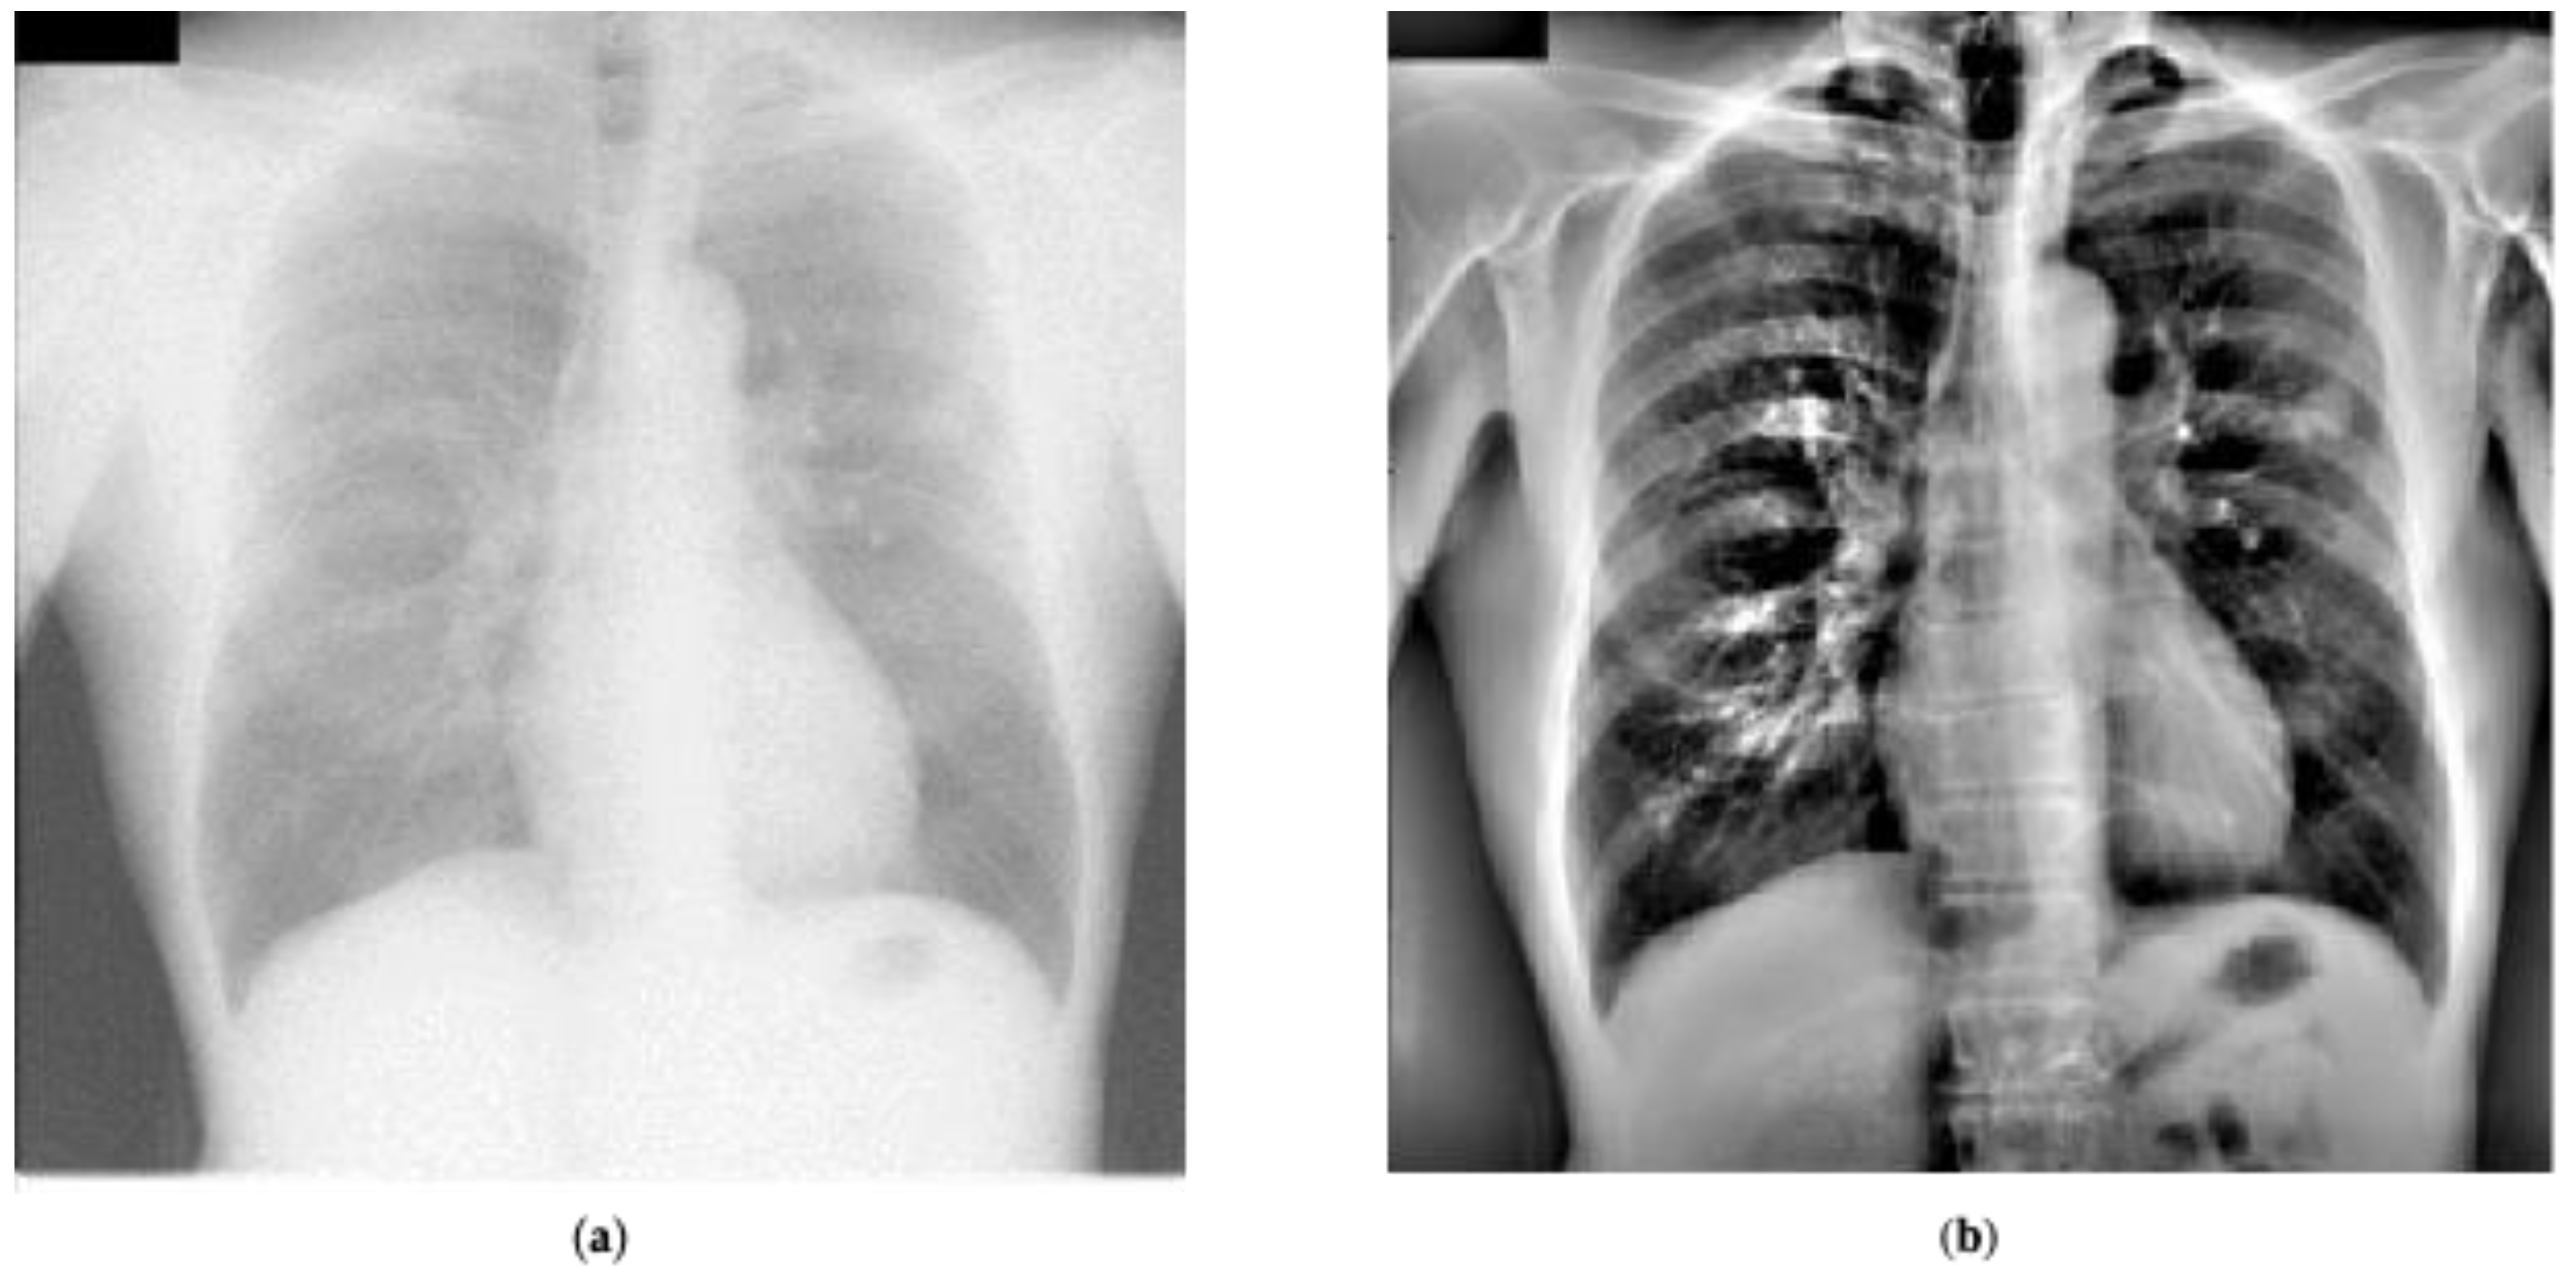

where m, n are pixel coordinates, y ( m , n ) represents the LCE image, x ( m , n ) represents the resized image, σ ( m , n ) is the local standard deviation estimate, and μ ( m , n ) represents the local spatial mean estimate. Local spatial mean and standard deviations were estimated by convolving the resized images with a Gaussian low pass filter that had a standard deviation of 16 [5]. Figure 8 shows an example image from the JRST dataset before and after LCE preprocessing.

Figure 8. An example from the JRST dataset: (a) raw image, (b) preprocessed image.